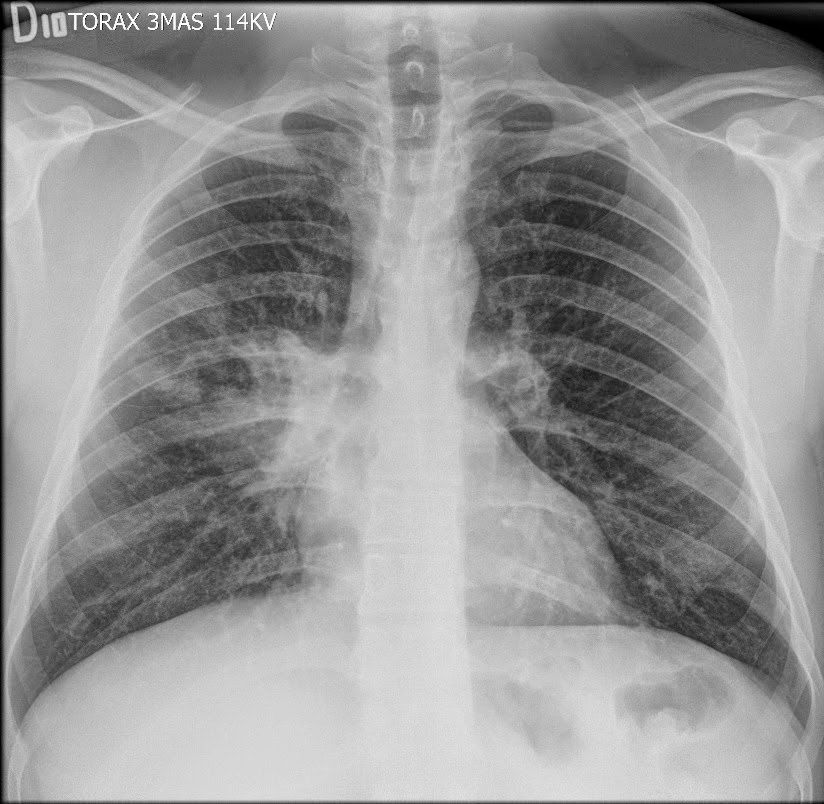

Caso interesante #2

¿A QUE CORRESPONDE Y PORQUE SE PRODUCE ESTA IMAGEN

IMÁGENES RADIOLÚCIDAS BILATERALES EN FORMA DE LUNA MENGUANTE ADYACENTE A LAS CABEZAS HUMERALES??????